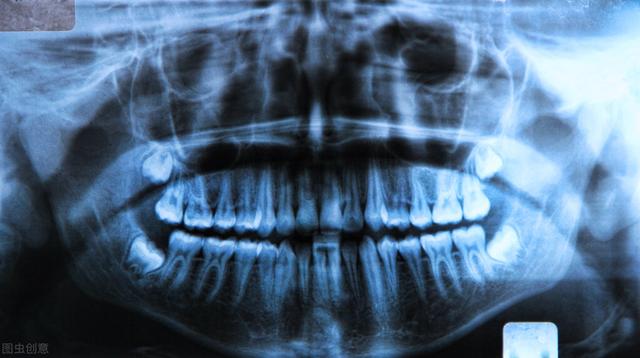

·球上颌囊肿:上颌切牙与尖牙之间的牙齿受到倾轧 导致错位,使牙根之间发生囊肿;

·本腭囊肿:发病部位在牙切管内部或者是牙切管周围 部位,生长缓慢,但很容易造成牙齿排序庞杂导致咬合杂乱 。

·正中囊肿:发生部位在上颌骨与下颌骨团结 位置的正中央 ;由突出腭部或团结 处周围 残余上皮组织病变引起的。

·鼻唇囊肿:30-50岁成年女性患病较多,位于上牙床底和鼻前庭内,大多是由鼻泪管周围 的上皮组织病变引起的。